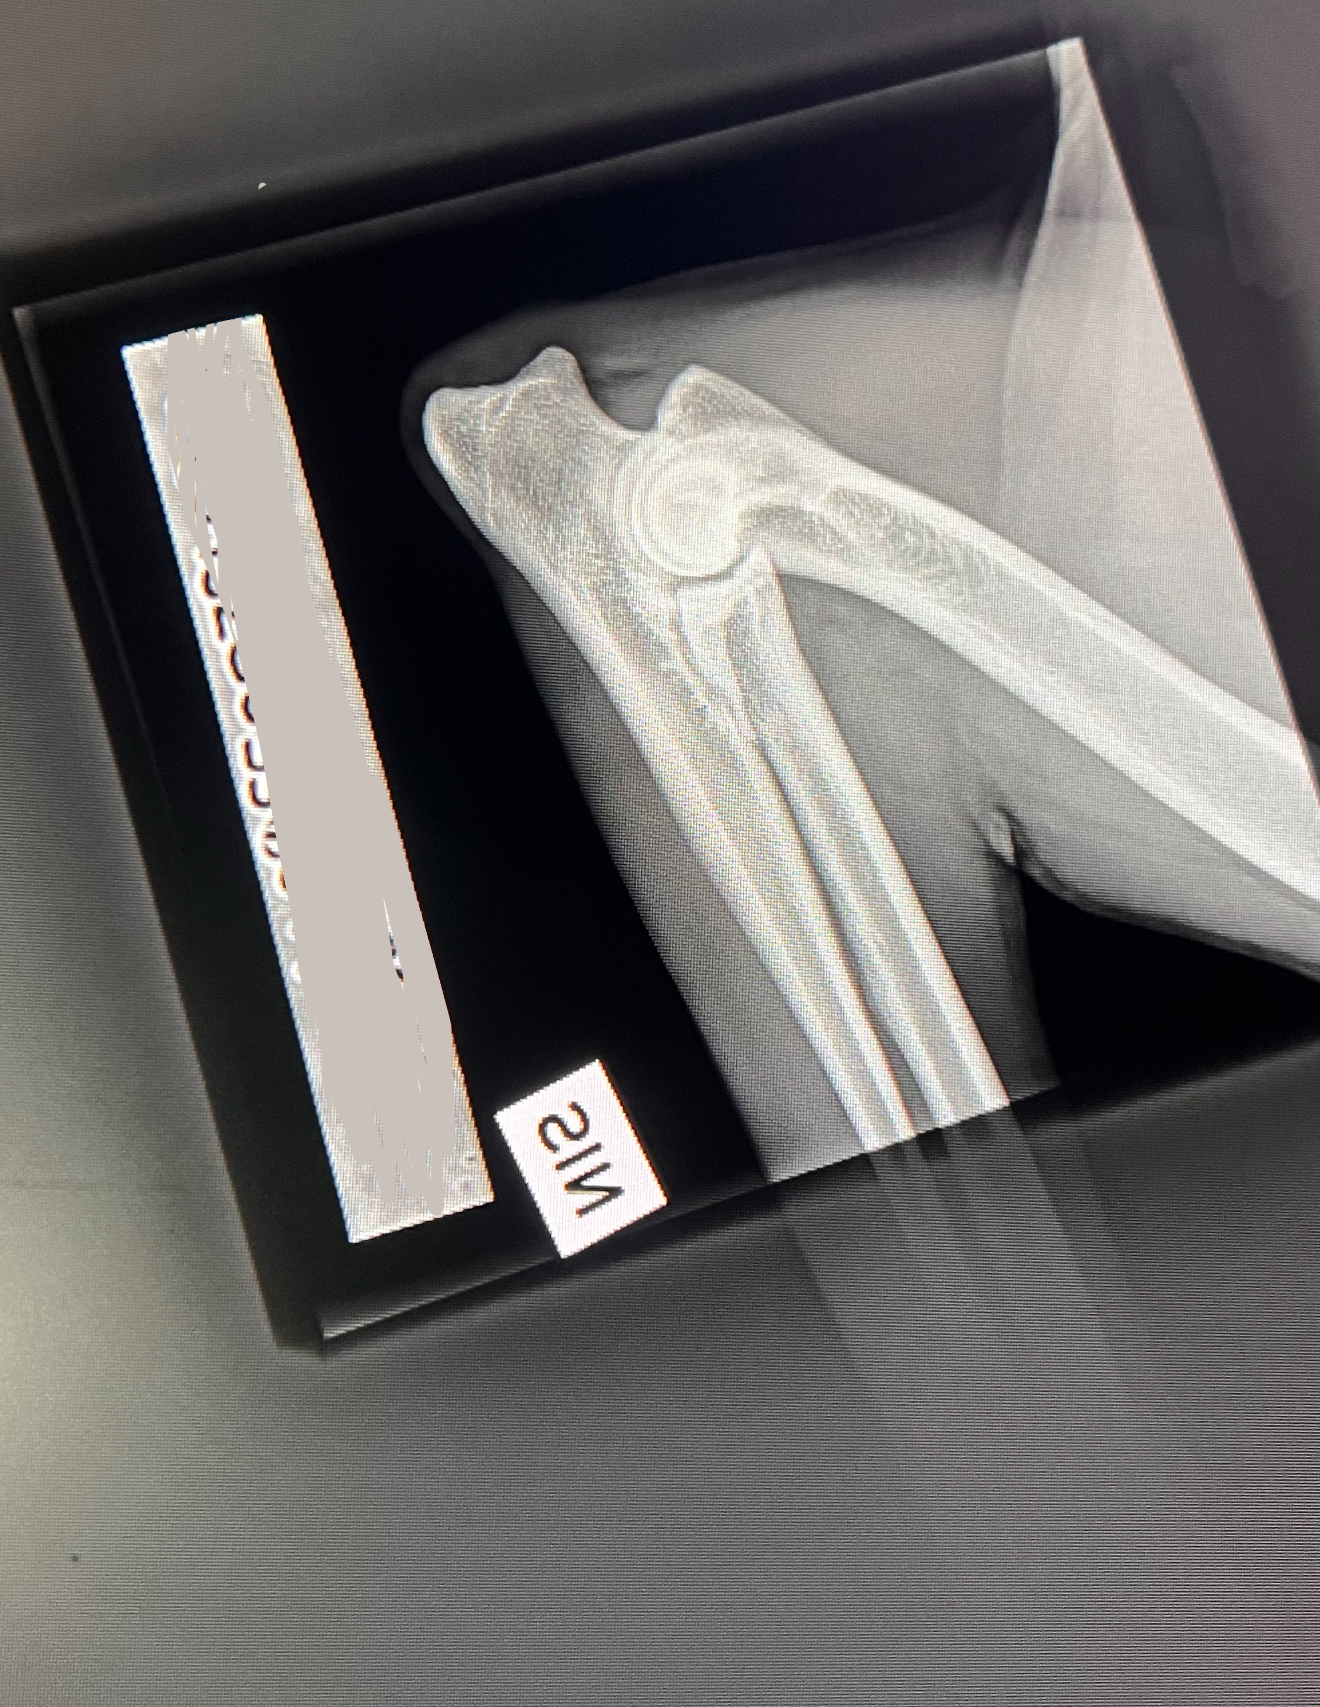

Och ja – vi röntgar även katter! 🐱 På sista bilden ser ni en HD-bild på en Maine Coon.